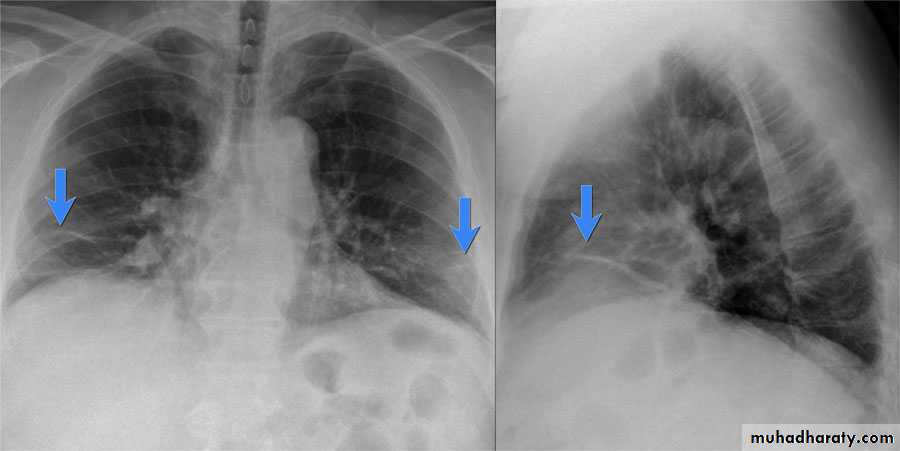

Patient with fever, rigor and dyspnea

Differential diagnosis?